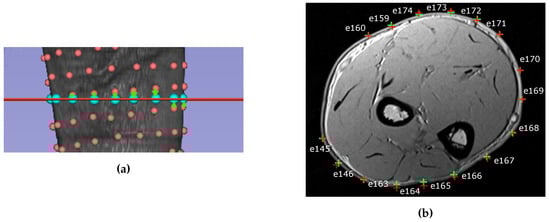

To correctly place the electrodes on the MRI volume a registration step has been done prior to the creation of the model, since electrodes’ coordinates and MRI anatomy have been acquired with different reference frames. Registration estimates the optimal transformation to match the coordinate system of the electrodes to the coordinate system of the MRI. The registration has been done using 3D slicer [23,24], minimizing the distance between the anatomical markers on the MRI and the markers acquired with the electrodes coordinates using the digitizer. The electrodes around the arm that were closest to the chosen slice were selected and their 2D projection on the MRI section was calculated (Figure 4a). The position of the electrodes on the slice was set as the closest point on the skin of the projected electrodes (Figure 4b). The mean and the maximum distance error made during electrodes’ projections steps are reported in Table 1 for all subjects. On the upper rows the errors for the projection on the selected slice are reported while on lower rows the errors on the projection on the skin surface are reported. On average the error during the projection on the selected slice is between 3 and 4.2 mm, with maximum values ranging from 7.5 to 11 mm. The distance errors on the projection on the skin surface was lower, with an average error smaller than 1 mm for all subjects and maximum values going from 1.5 to 3 mm.

Figure 4. (a) The projection of the electrodes closest to the selected slice plane. The real electrodes position is indicated with a red sphere, the MRI plane is indicated with a red line and the projected position is indicated with a light blue sphere. The projection is depicted with a green arrow. (b) Section of the MRI with the position and the number of the electrodes. The projection of the electrode 3D position on the 2D slice is represented with a red cross. Such points are further projected on the skin (green cross) to find the closest position on the forearm surface.